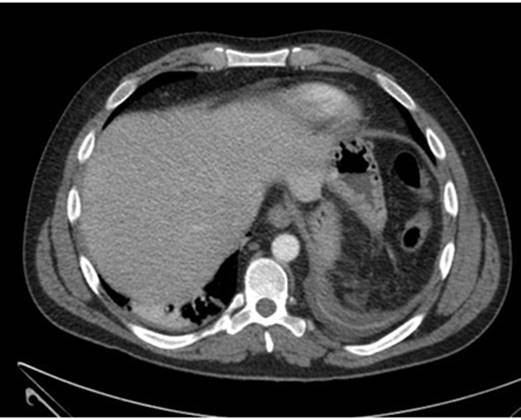

Se completa el estudio de imagen con Ecografía abdominal y Tomografía Axial Computarizada abdominal (Figura 2) urgente que muestra hematoma subcapsular de 14 x 4,5 x 12,5 cm. Posteriormente, el paciente presenta inestabilidad hemodinámica y anemización progresiva, precisando drogas vasoactivas y siendo intervenido de laparotomía exploradora urgente, realizándose esplenectomía total y limpieza de la cavidad peritoneal. Una vez que se encuentra estable tras la intervención es dado de alta tras nueve días de hospitalización.